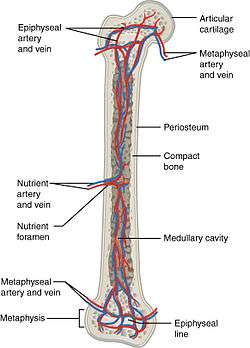

The blood supply to long bones, here with nutrient artery, vein and foramen labeled. | |

All bones possess larger or smaller foramina (openings) for the entrance of the nourishing blood-vessels; these are known as the nutrient foramina, and are particularly large in the shafts of the larger long bones, where they lead into a nutrient canal, which extends into the medullary cavity.[1] Along with veins the nutrient arteries pass through this canal. A nutrient canal is found in both long bones and in irregular bones. In long bones the nutrient canal is found in the shaft, and in irregular bones it is found in other locations.